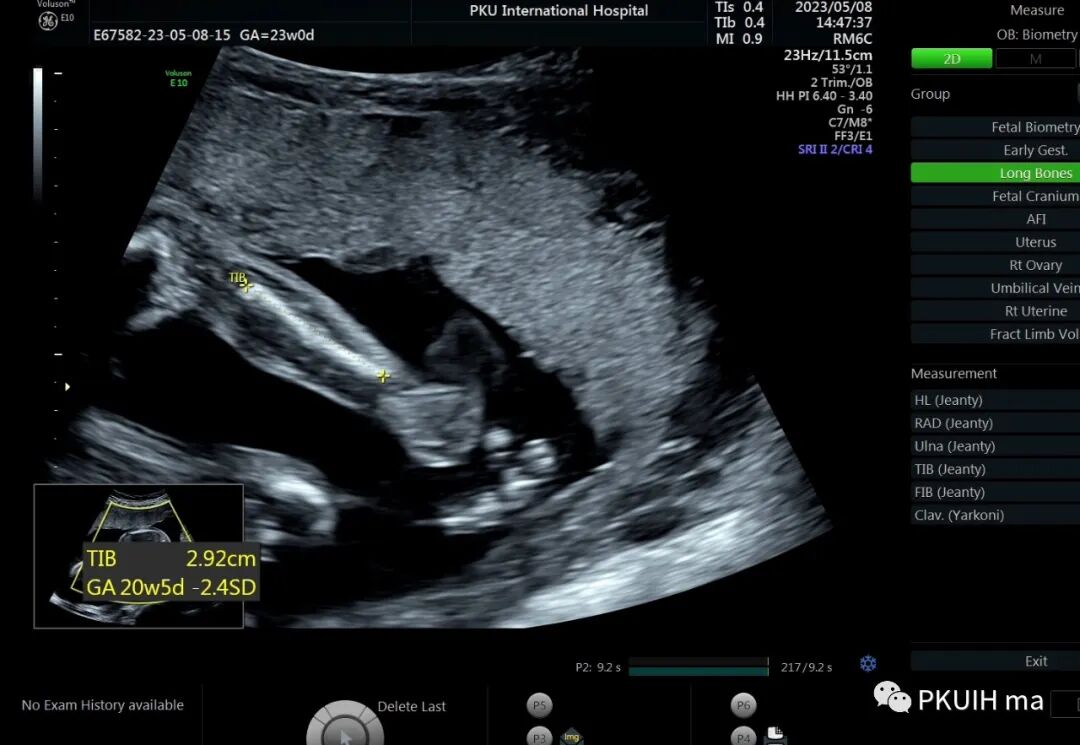

孕23周常规筛畸发现四肢长骨偏短,孕妇月经正常,核对早孕超声,孕周也没问题。

24周+复查发现还是肢体短,生长变慢

28周检查发现肢体越来越短